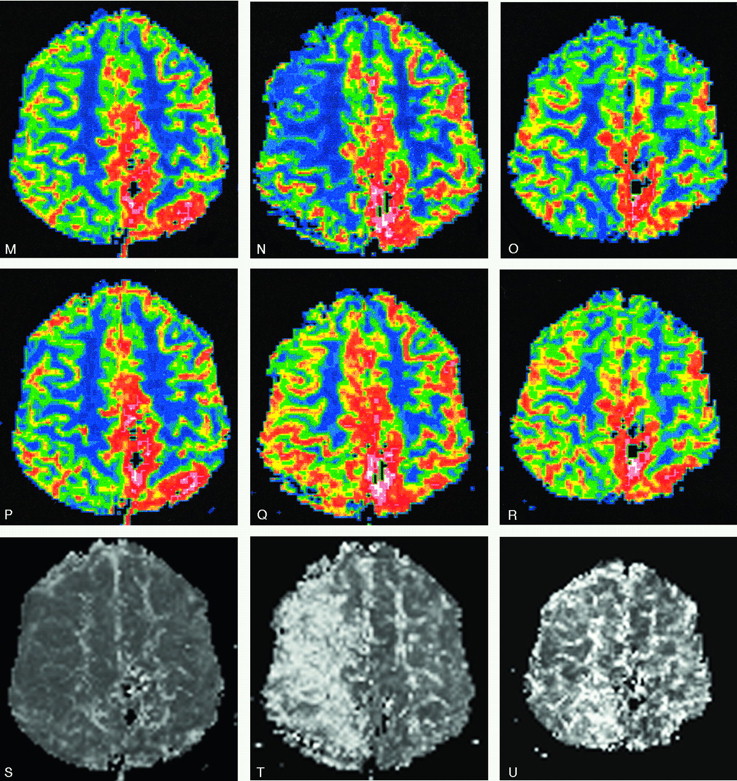

Parietal high-flow AVM with deep and bilateral cortical drainage.

A–D, Frontal left internal carotid angiogram, early and late phase, before and after the second embolization. Patent venous drainage is seen after the treatment.

E–L, Axial MR (E–H, T1-weighted, and I–L, DWI [b 1000]) immediately posttreatment, at 23 days, 35 days after treatment, and before a third treatment, 3 months later. The images illustrate the development of venous thrombosis 3 weeks after treatment in the deep and contralateral cortical veins with a complete resolution at follow-up.

M–U, rCBF (M–O) and rCBV (P–R) with the corresponding MTT (S–U): unchanged PI images after treatment (left column) are followed by a dramatic increase in MTT (severe drop in rCBF with a mild rCBV increase) 3 weeks later (middle column). A slow but almost total normalization of PI pattern was seen 9 days later (ie, after hypervolemic hemodilution) (right column). The patient was left with no symptoms.

New MR Imaging Patterns, including DWI and PI, Evolving between Procedures

New MR imaging abnormalities were noted between treatments in 3 patients. Pure progressive venous outlet thrombosis associated with an “asymptomatic” ICH (subacute hematoma in resolution) was found in one patient and a severely disturbed perfusion pattern with increased MTT in a second (Fig 4). The latter occurred contralaterally to the embolized AVM. Following a week of conservative medication therapy and regular MR imaging monitoring, PI ultimately returned to normal (see discussion below). A more extensive thrombosis involving the feeding artery, the nidus, and, in particular, the draining vein, was seen in the third patient and resulted in vasogenic edema in the white matter with a matching PI defect (Fig 5).

Two patients (discussed above) with venous thrombosis progressing between the treatments showed impaired perfusion. In the patient with extensive vasogenic edema, perfusion was decreased (both rCBF and rCBV). Following treatment, however, the edema was almost totally reabsorbed and the PI ameliorated (Fig 5). Plausibly, the edema was caused by locally increased perfusion pressure, induced by the venous outflow obstruction, that was eliminated instantly with the reduction of the AVM shunt. The second patient presented with minor left-sided symptoms 3 weeks after an uneventful treatment of a high-flow AVM in the left cerebral hemisphere. Although no signs of ischemia were detected on DWI, PI revealed a severely disturbed and prolonged MTT (reduced rCBF and moderately increased rCBV) in the right hemisphere (Fig 4). Re-evaluation of the postprocedural DSA confirmed patent vessels with the draining veins free from stagnation and glue. Following treatment with intravenous heparin and hypervolemic hemodilution, the patient became asymptomatic and the PI pattern was almost normalized within 9 days.

Because, in this patient, the brain could not compensate for the diminished perfusion by progressive vasodilation, we assume that rCBF had begun to fall. The compensatory vasodilation in response to increased rCBV, normally seen in arterial occlusions, appears to be less pronounced with hypoperfusion emanating from a venous occlusion, probably because the venous system is then forced to work against a higher pressure gradient.

Although our understanding of the complex pattern of cerebral autoregulation and PI findings is still incomplete, we could nevertheless use the information from PI to estimate the degree of variations in cerebral perfusion and initiate appropriate treatment.